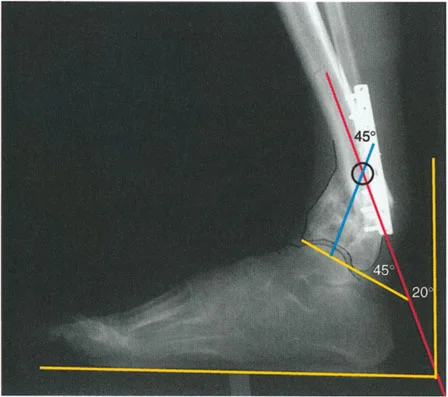

* الأشعة السينية الجانبية والامامية الخلفية للكاحل: تُظهر هذه الصور تفاصيل مفصل الكاحل نفسه، بما في ذلك زاوية القصبة الأمامية البعيدة (ADTA) وزاوية القصبة الوحشية البعيدة (LDTA)، وهي زوايا حاسمة لتحديد التشوه في المستويين الأمامي والسهمي.

* منظر سولتزمان (Saltzman View): هذا المنظر الإشعاعي الخاص يتم الحصول عليه بزاوية 20 درجة لقياس محاذاة عظم العقب (Calcaneus) بالنسبة لقصبة الساق، وهو أمر بالغ الأهمية لتقييم تعويضات القدم الخلفية.

* رسم المحاور الميكانيكية والتشريحية: لتحديد نقطة مركز دوران التشوه (CORA)، وهي النقطة التي يجب أن تتم عندها الجراحة لتصحيح التشوه بأقل قدر من المضاعفات.

تُعد مبادئ الدكتور درور بالي حجر الزاوية في جراحة تصحيح تشوهات العظام. تركز هذه المبادئ على تحديد "مركز دوران التشوه" (CORA - Center of Rotation of Angulation) بدقة. إن موقع CORA يحدد كيفية تأثير التشوه على المفاصل المجاورة ويوجّه الجراح في اختيار مكان قطع العظم (Osteotomy).

• قواعد بالي لقطع العظم:

1. القاعدة الأولى: عندما يمر قطع العظم ومحور تصحيح الزاوية (ACA) عبر CORA، يتم تحقيق تصحيح زاوي نقي دون أي إزاحة.

2. القاعدة الثانية: عندما يمر ACA عبر CORA، ولكن قطع العظم يتم في مستوى مختلف (غالبًا ما يكون ضروريًا لتوفير مساحة كافية للتثبيت)، يتم تحقيق تصحيح زاوي نقي، ولكن أطراف العظم ستنزاح في موقع قطع العظم. يجب على الجراح توقع هذه الإزاحة وإدارتها.

3. القاعدة الثالثة: إذا كان ACA وقطع العظم في نفس المستوى، ولكن لا يمر أي منهما عبر CORA، فسيحدث تشوه إزاحة (ترجمة) غير مرغوب فيه. يتطلب هذا الأمر من الجراح إجراء إزاحة متعمدة للقطعة العظمية البعيدة أثناء التصحيح الزاوي لإعادة محاذاة المحور الميكانيكي.